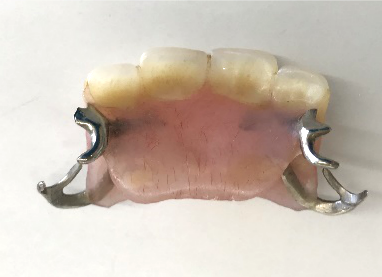

使用していた部分入れ歯